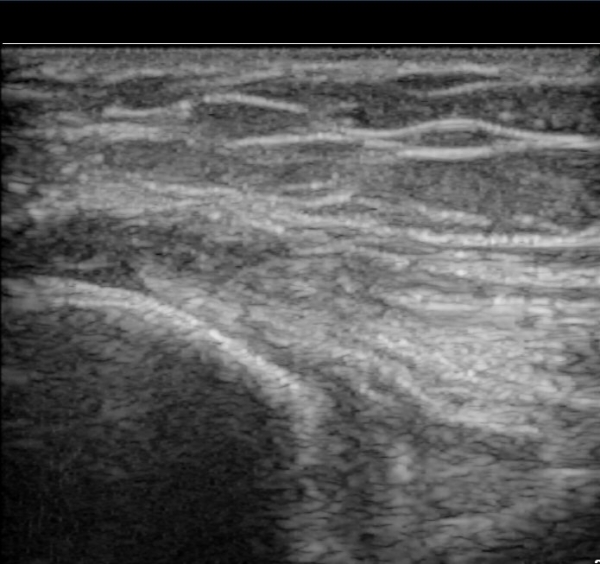

ŽÃËÀÚ¸¦ Á¶±Ý À̵¿ÇÏ´Ï °Ç ÀϺδ Á¤»óÀûÀÎ ¼Ò°ßÀ» º¸À̰í ÀÖ´Ù(±×¸² 3).

°í¿¡ÄÚ Å½ÃËÀÚ(ÇÏŰ½ºÆ½)·Î °üÂû ½Ã °Ç ºÎÂøºÎ°¡ °í¿¡ÄÚ ¼¶À¯ ¾ç»óÀ¸·Î Á¤»óÀûÀÎ ¼Ò°ßÀ» º¸ÀδÙ(±×¸² 4).